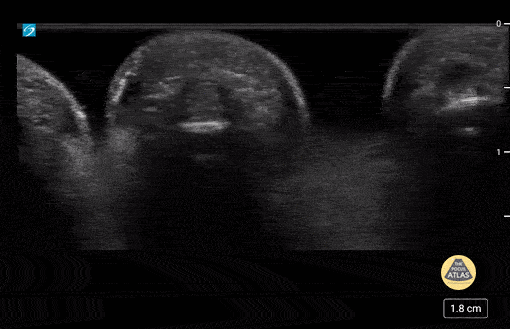

5 yo with normal finger anatomy in a waterbath. Case series 1/2 Contributor: Paul Khalil, MD Nicklaus Children's Hospital @khalil3paul